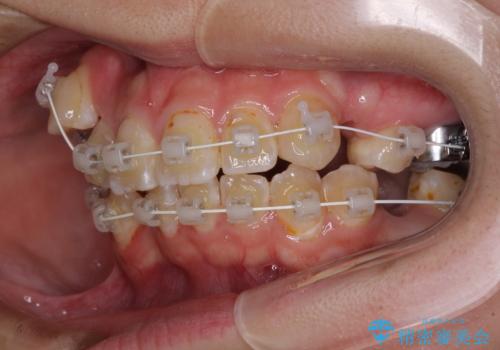

- 審美装置

- 八重歯や埋伏している奥歯など、多くの難しい問題を抱えている患者様です。

重度叢生のため、大臼歯をしっかりと咬合させるために、下顎は左右第二小臼歯を、上顎は前歯部の叢生を解消するために左右第一小臼歯を抜歯し、口元の突出感を改善するために、上顎大臼歯が前方に移動しないようにするために、補助装置による架強固定を行うこととしました。

叢生は思ったよりも早期に改善されましたが、舌の突出癖による上下前歯の非接触が全く改善されず、2年間ほど治療期間が延びる結果となってしまいました。